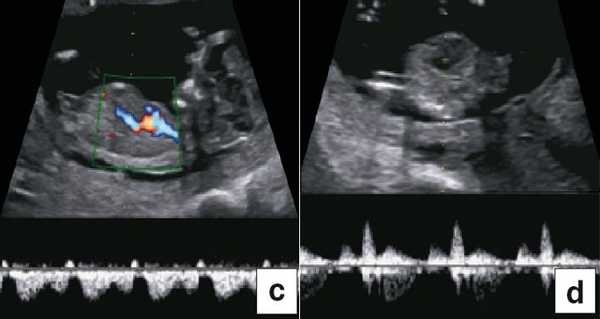

Диагноз хориальности и количества амнионов

УЗИ при двойне в основном должно выявить хориальность (ди- или монохориальность) и для монохориальных беременностей (моно- или диамниотических) - количество амнионов. При многоплодной беременности эта информация необходима для соответствующего ведения дискордантной мальформации, замедления роста, внутриутробной гибели плода или получения образцов ткани плода. Точность этой диагностики в течение I триместра может достигать 100%, а затем на протяжении беременности она уменьшается [7]. Дихориальность подтверждают выявлением лямбда-признака (рис. 4a). Наоборот, монохориальность диагностируют при отсутствии визуализации лямбда-признака или выявлении T-признака (рис. 4b) в межамниотической мембране, расположенной перпендикулярно хорионической пластине.

Рис. 4. Диагностика хориальности и количества амнионов в I триместре путем оценки лямбда-признака (a) и T-признака (b).